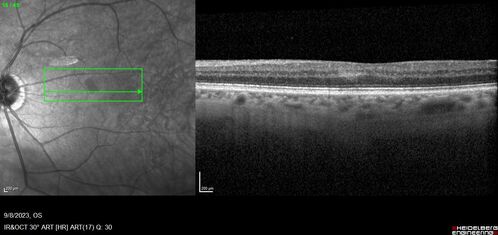

Paracentral acute middle maculopathy - isolated

83 year old man New spot in the vision yesterday left eye.

Medical Hx: Pure Hypercholesterolemia

Systemic Meds: Crestor.

VA OD: Dcc20/20

VA OS: Dcc20/20

IOP: TP: OD:19 OS:10

Isolated PAMM lesion